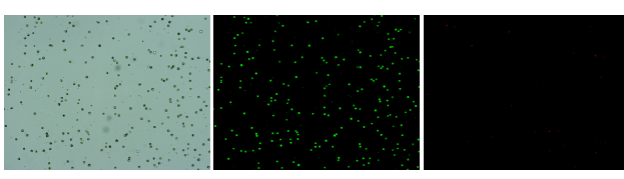

人肝癌樣本,懸液背景干凈,活性91.69%,結(jié)團(tuán)率6%